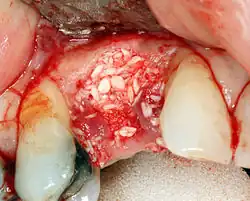

Реконструкция твёрдых тканей

Восстановление мягких тканей